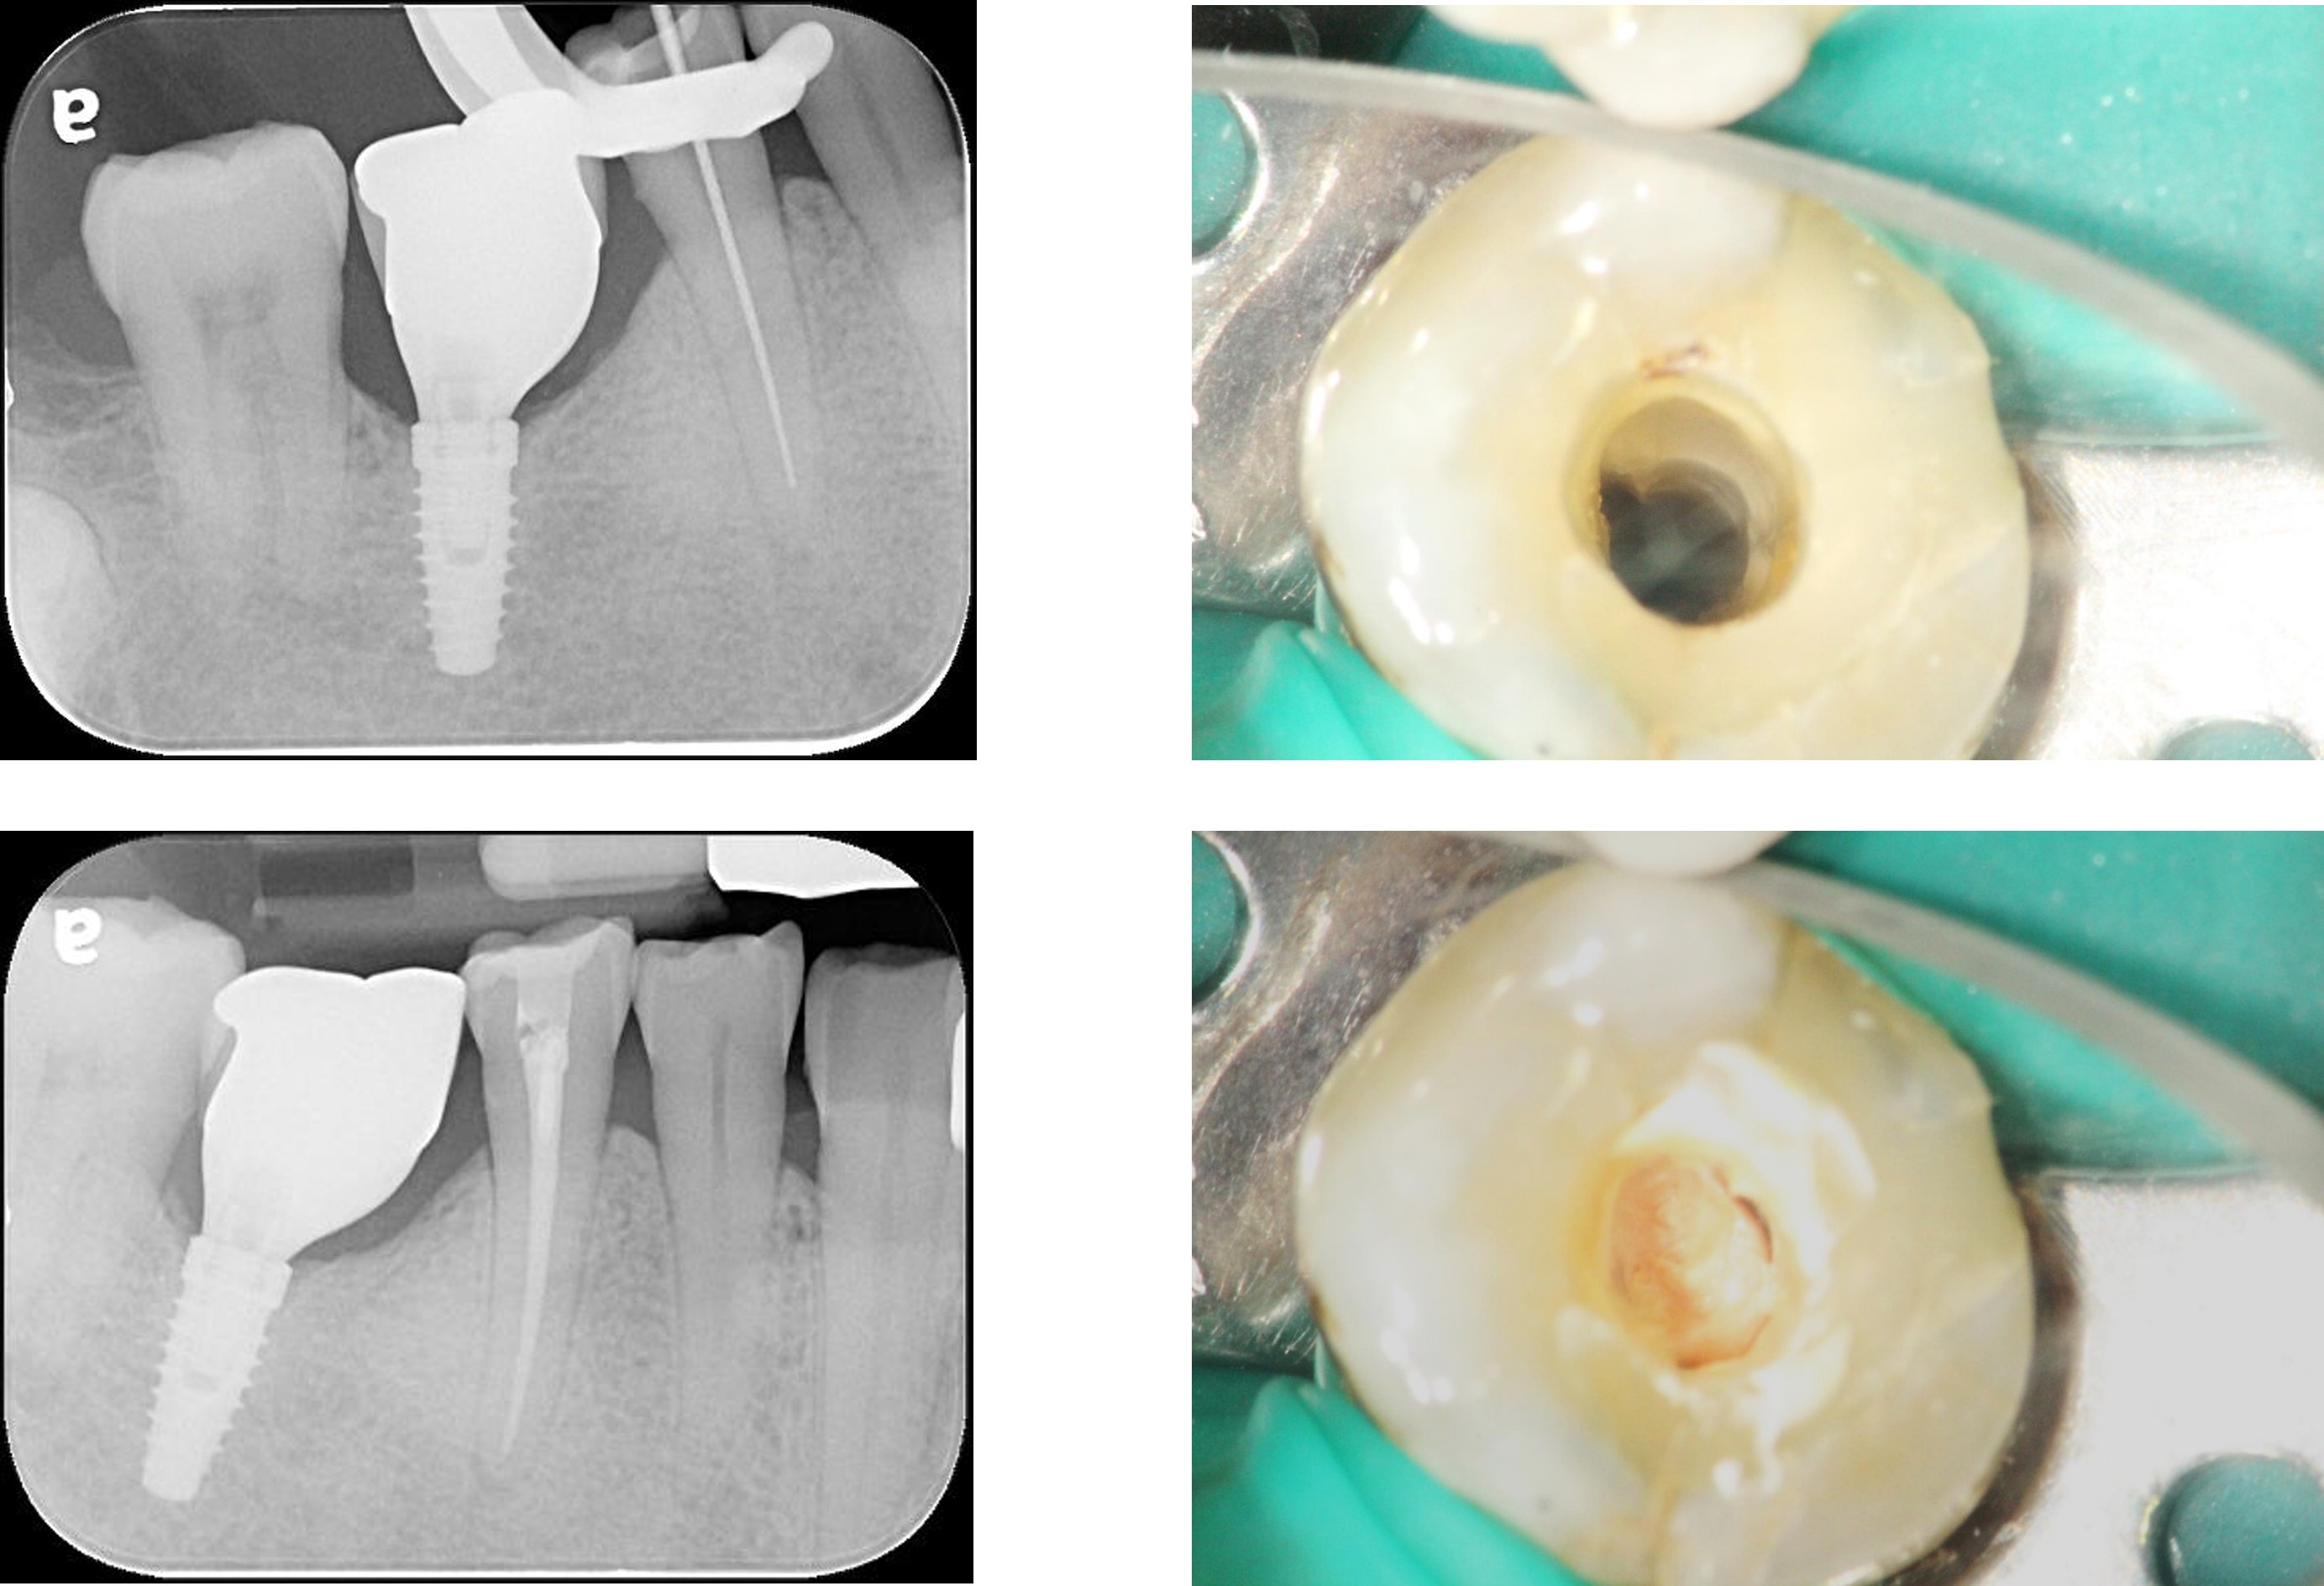

顯微根管治療

製作玻璃纖維釘